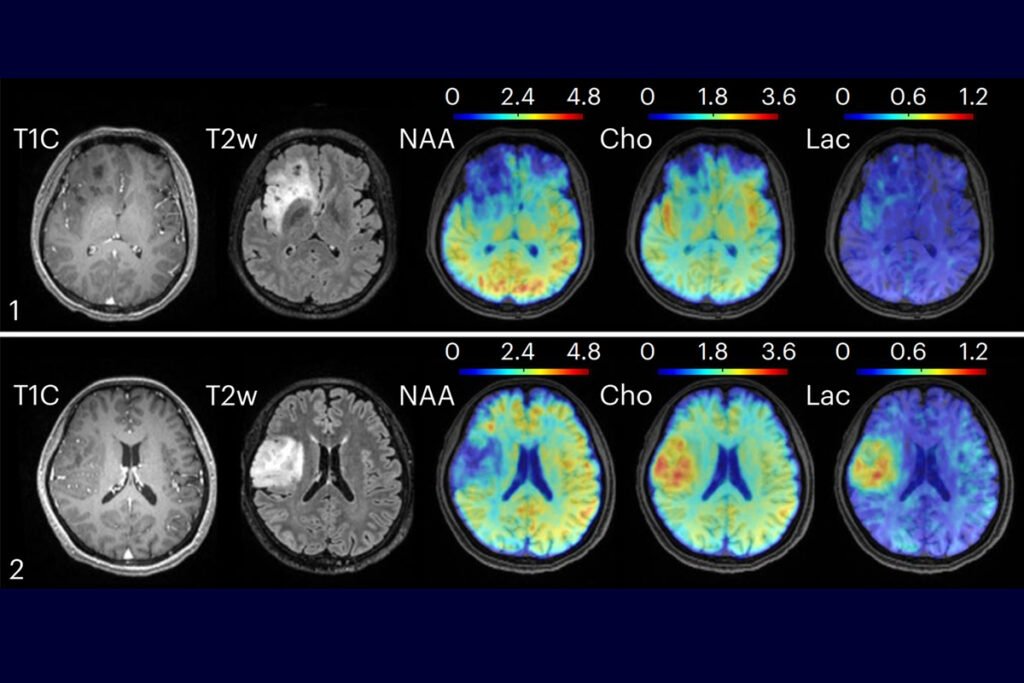

Delivering drugs to the brain has always been a high-stakes challenge. The blood-brain barrier (BBB)—a tightly regulated shield of cells—blocks over 98% of small molecule drugs, making treatment of neurodegenerative diseases like Alzheimer’s and Parkinson’s notoriously difficult. Now, researchers at […]